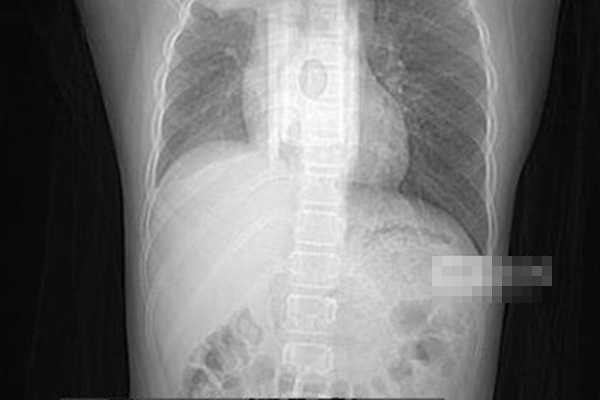

Phổi bé trai nổi nhiều mảng trắng.

Sau một loạt các cuộc kiểm tra, bác sĩ nhận định rằng, tình trạng của Zhou Zhou đã phát triển thành viêm phổi. Từ những bức ảnh siêu âm có thể thấy một bên mô phổi của cậu bé có một mảng trắng lớn.